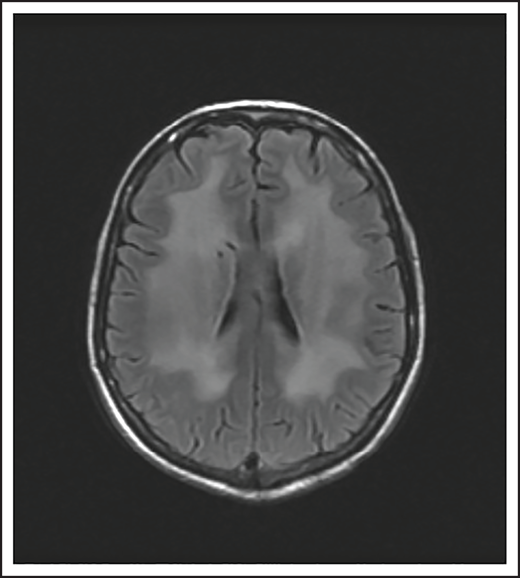

A 24-year-old man presented with stage IVB DLBCL and completed 6 cycles of R-CHOP, with FDG-PET after treatment showing resolution of all disease except in the mediastinum. After a biopsy of this residual FDG+-confirmed DLBCL, he received treatment with salvage chemotherapy with minimal response, followed by mediastinal involved field radiation therapy (IFRT) to a dose of 40 Gy plus a 6-Gy boost, after which he had a CR. Subsequently, he underwent autologous SCT followed by RIC allogeneic SCT. He remained in CR for 16 months, at which time he presented with 3 weeks of new right leg weakness, erectile dysfunction, and urinary hesitancy. The results of a brain MRI were unremarkable, but a spine MRI demonstrated spinal cord expansion and edema with multifocal enhancement within the prior radiation therapy portal from T5 to T9, demarcated by fatty marrow replacement between the T5 and T9 vertebral bodies (Figure 4). A diagnostic evaluation, including CSF analysis, was negative for malignancy, infection, autoimmune or inflammatory conditions, or demyelination. He was diagnosed with radiation-induced myelitis. He was treated with HD-MTX and had a minimal response. Treatment with bevacizumab led to complete resolution of the lesion, and after intensive physical therapy, he regained neurologic function.

MRI of the cervical and thoracic spine of a patient with radiation-induced myelopathy. (A) Axial T1-weighted image after gadolinium contrast shows enhancement within the spinal cord. (B) Sagittal T2 image shows a signal change throughout the patient’s prior radiation portal from T5 to T9, demarcated by fatty marrow replacement between the T5 and T9 vertebral bodies.

Ionizing radiation to the brain or spinal cord can cause acute, subacute, or delayed adverse effects.58 Acute brain toxicity from radiation is typically related to cerebral edema and/or raised intracranial pressure and resolves with corticosteroids. Subacute effects caused by radiation-induced necrosis occur weeks to months after radiation and usually present with headache, lethargy, and focal neurologic deficits. Rarely, radiation myelopathy can result from focal radiation delivered to the mediastinum for HL and NHL, as in case 5.61 Spine MRI typically shows contrast enhancement within the spinal cord, and symptoms may resolve with corticosteroids. Bevacizumab has been used to treat radiation necrosis, as described in our case.62 Delayed neurotoxicity typically presents years after treatment. It can present as radiation-induced vasculopathy resulting in strokes or hemorrhage, or as brain atrophy and leukoencephalopathy. Older age and concurrent use of HD-MTX increase this risk.63